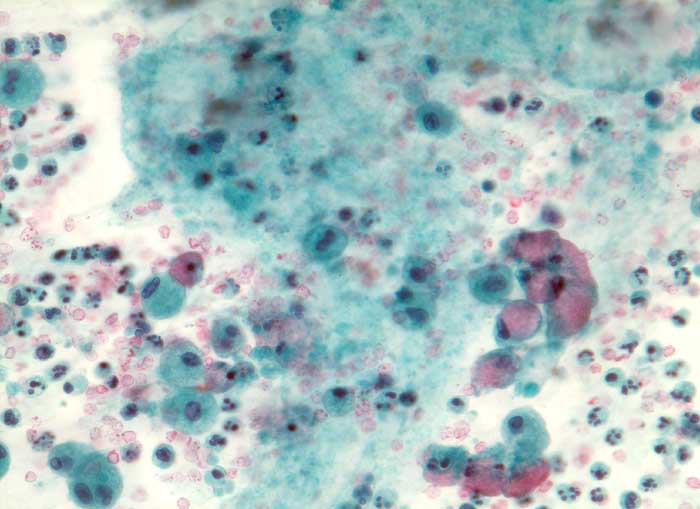

Muzinöses Zystadenom

benigner Tumor

Ovar

Ovarialzysteninhalt: Neben reichlich frischem und älterem Blut mit neutrophilen Granulozyten sowie Makrophagen und Detritus hin und wieder becherzellartig aufgetriebene schleimbildende Zylinderzellen ohne Atypien

Schleim++

Altes Blut+

Granulozyten+

Histiozyten(+)

Makrophagen++

Histiozytäre Riesenzellen(+)

Schleimbildende Zylinderzellen(+)

"Ovarialzyste" (gross) Dm 20cm.

Da hochdifferenzierte muzinöse Karzinome bisweilen kaum Atypien aufweisen, ist die sorgfältige Untersuchung des Operationspräparates notwendig (mindestens 1 Block pro cm Tumordurchmesser)

Zytologie

320